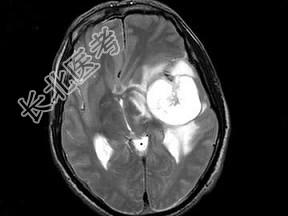

- 单项选择题男,51岁, 1个月前开始头痛,头昏, 根据所提供图像,最可能的诊断是 ( )

A、血管母细胞瘤

B、动脉瘤

C、少枝胶质细胞瘤

D、胶质瘤

E、转移瘤